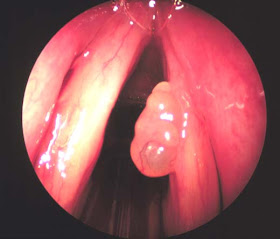

Single Laryngeal papilloma